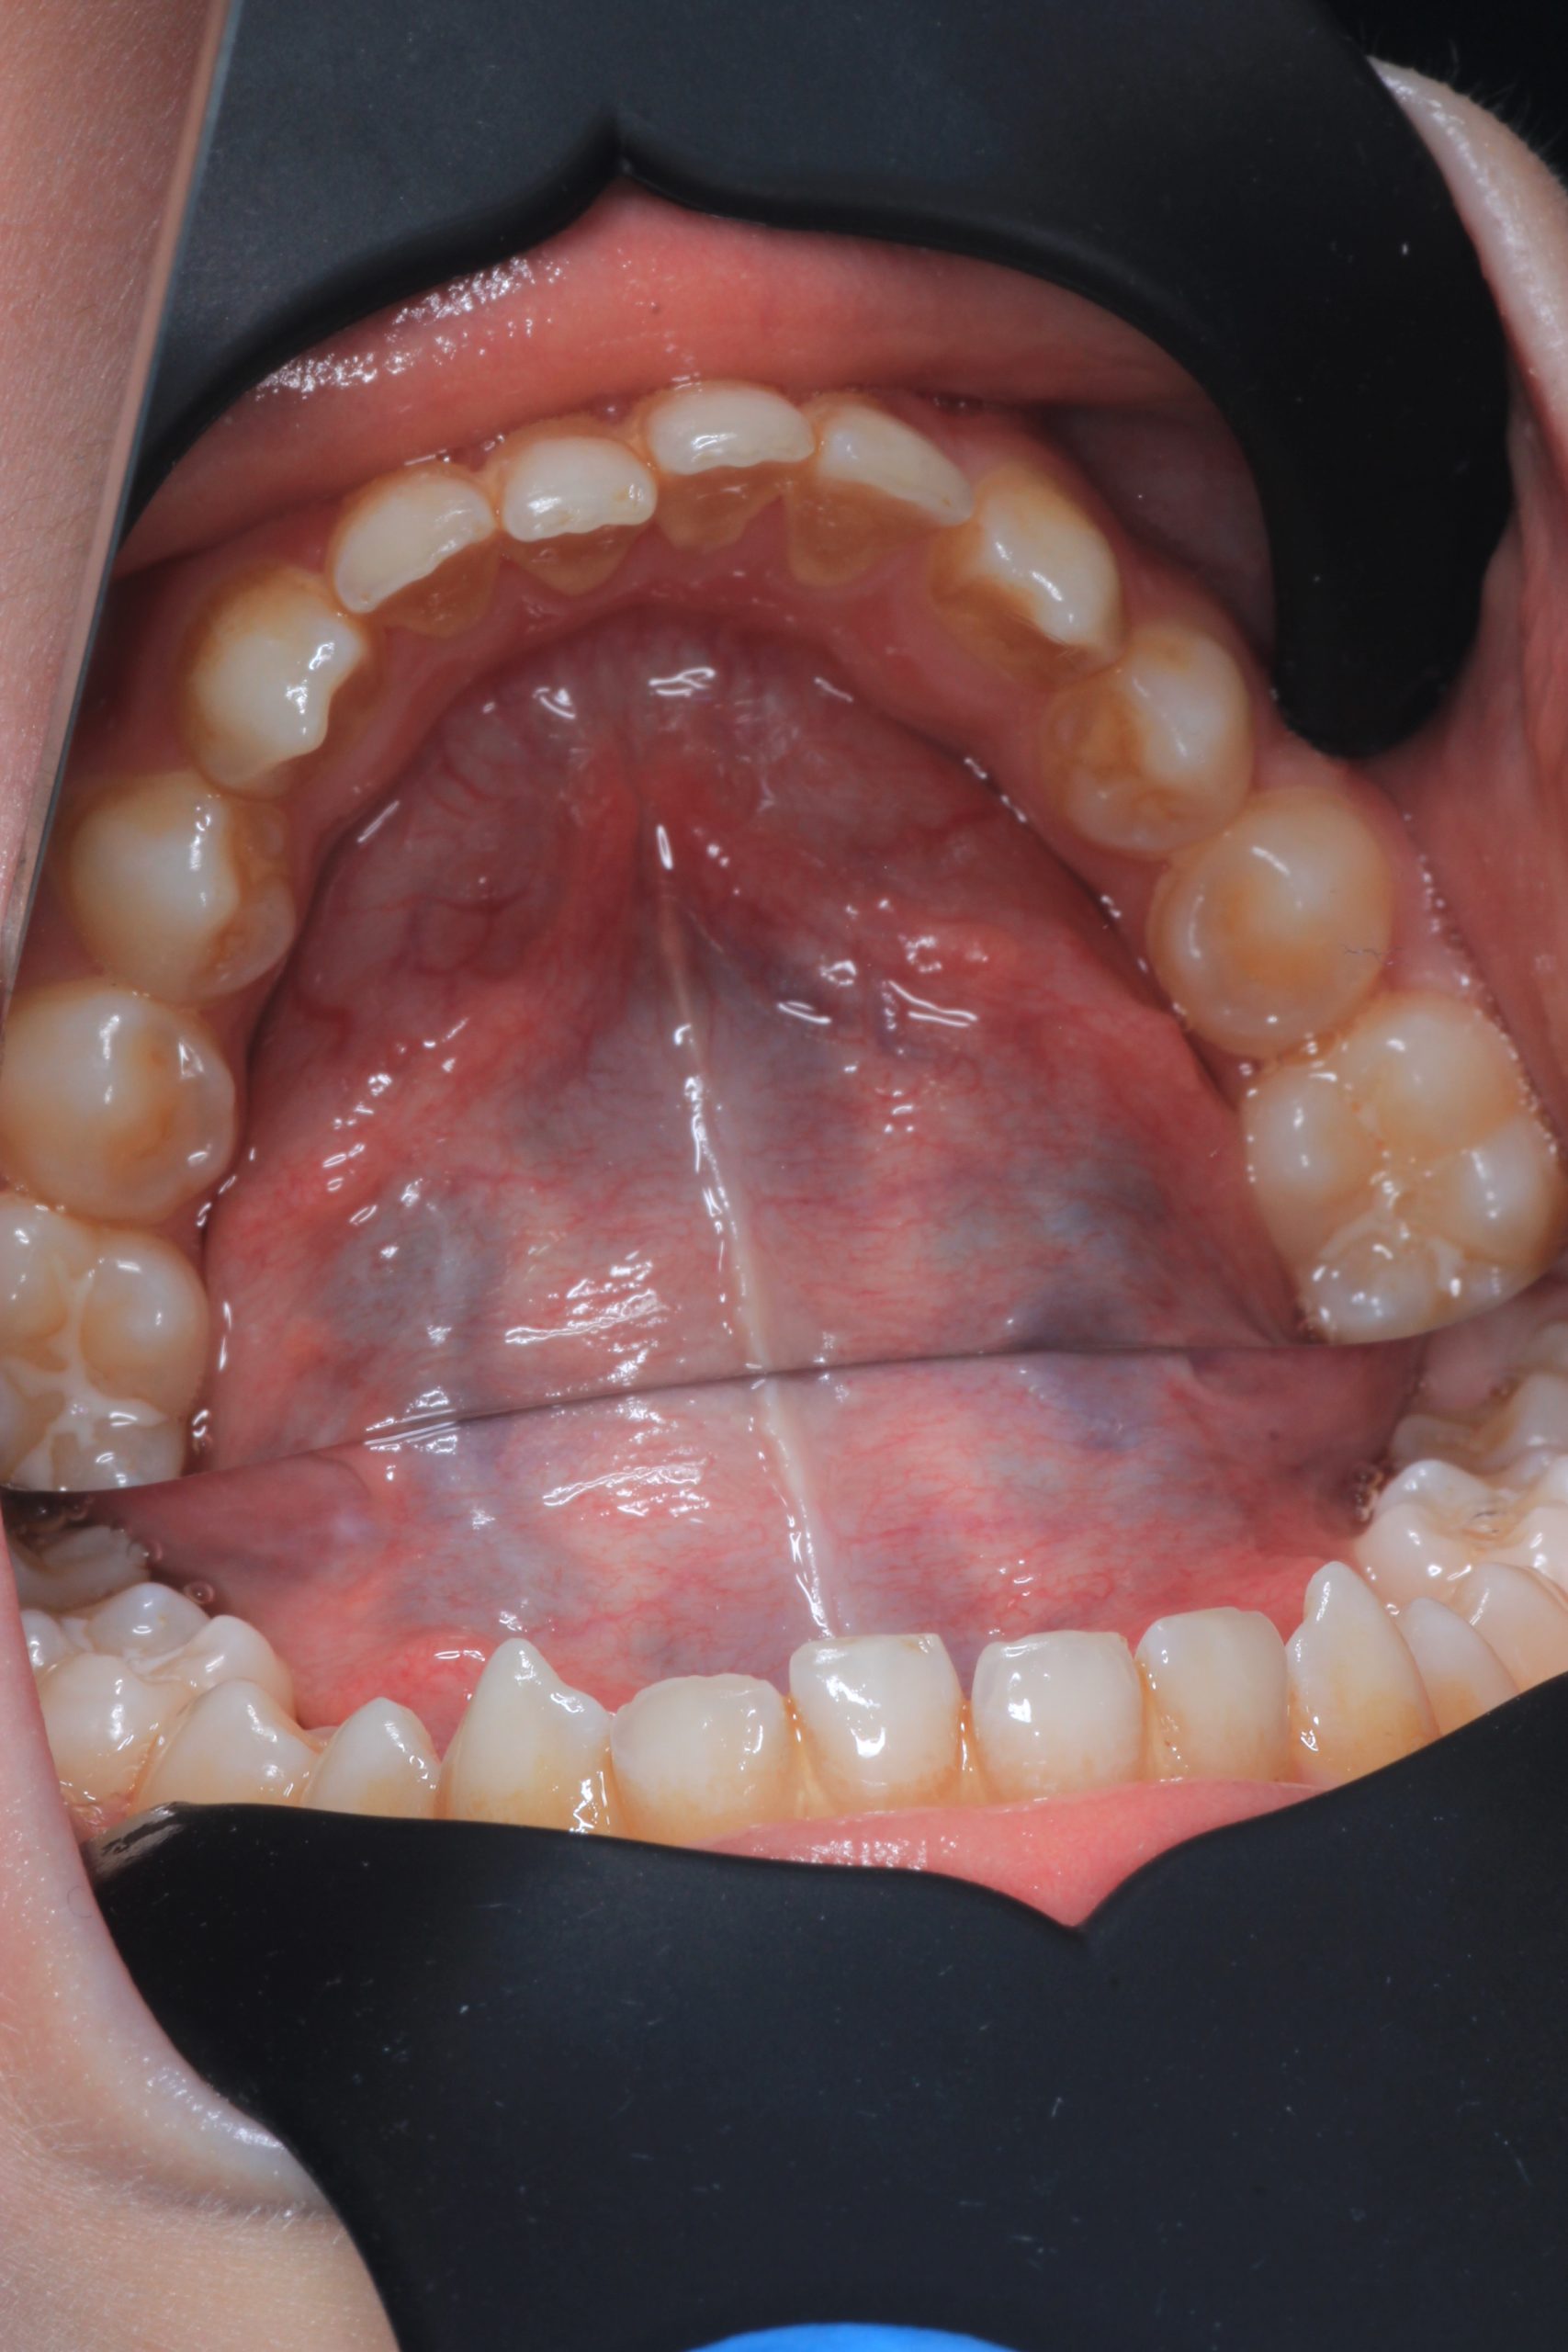

We examine the condition of teeth, gums, and bite. - Plaque Disclosure with Special Indicators

Areas that weren’t cleaned well appear purple. The darker the shade, the older the plaque. This helps both kids and parents understand where brushing needs to improve. - Brushing Training & Home Care Tools Selection